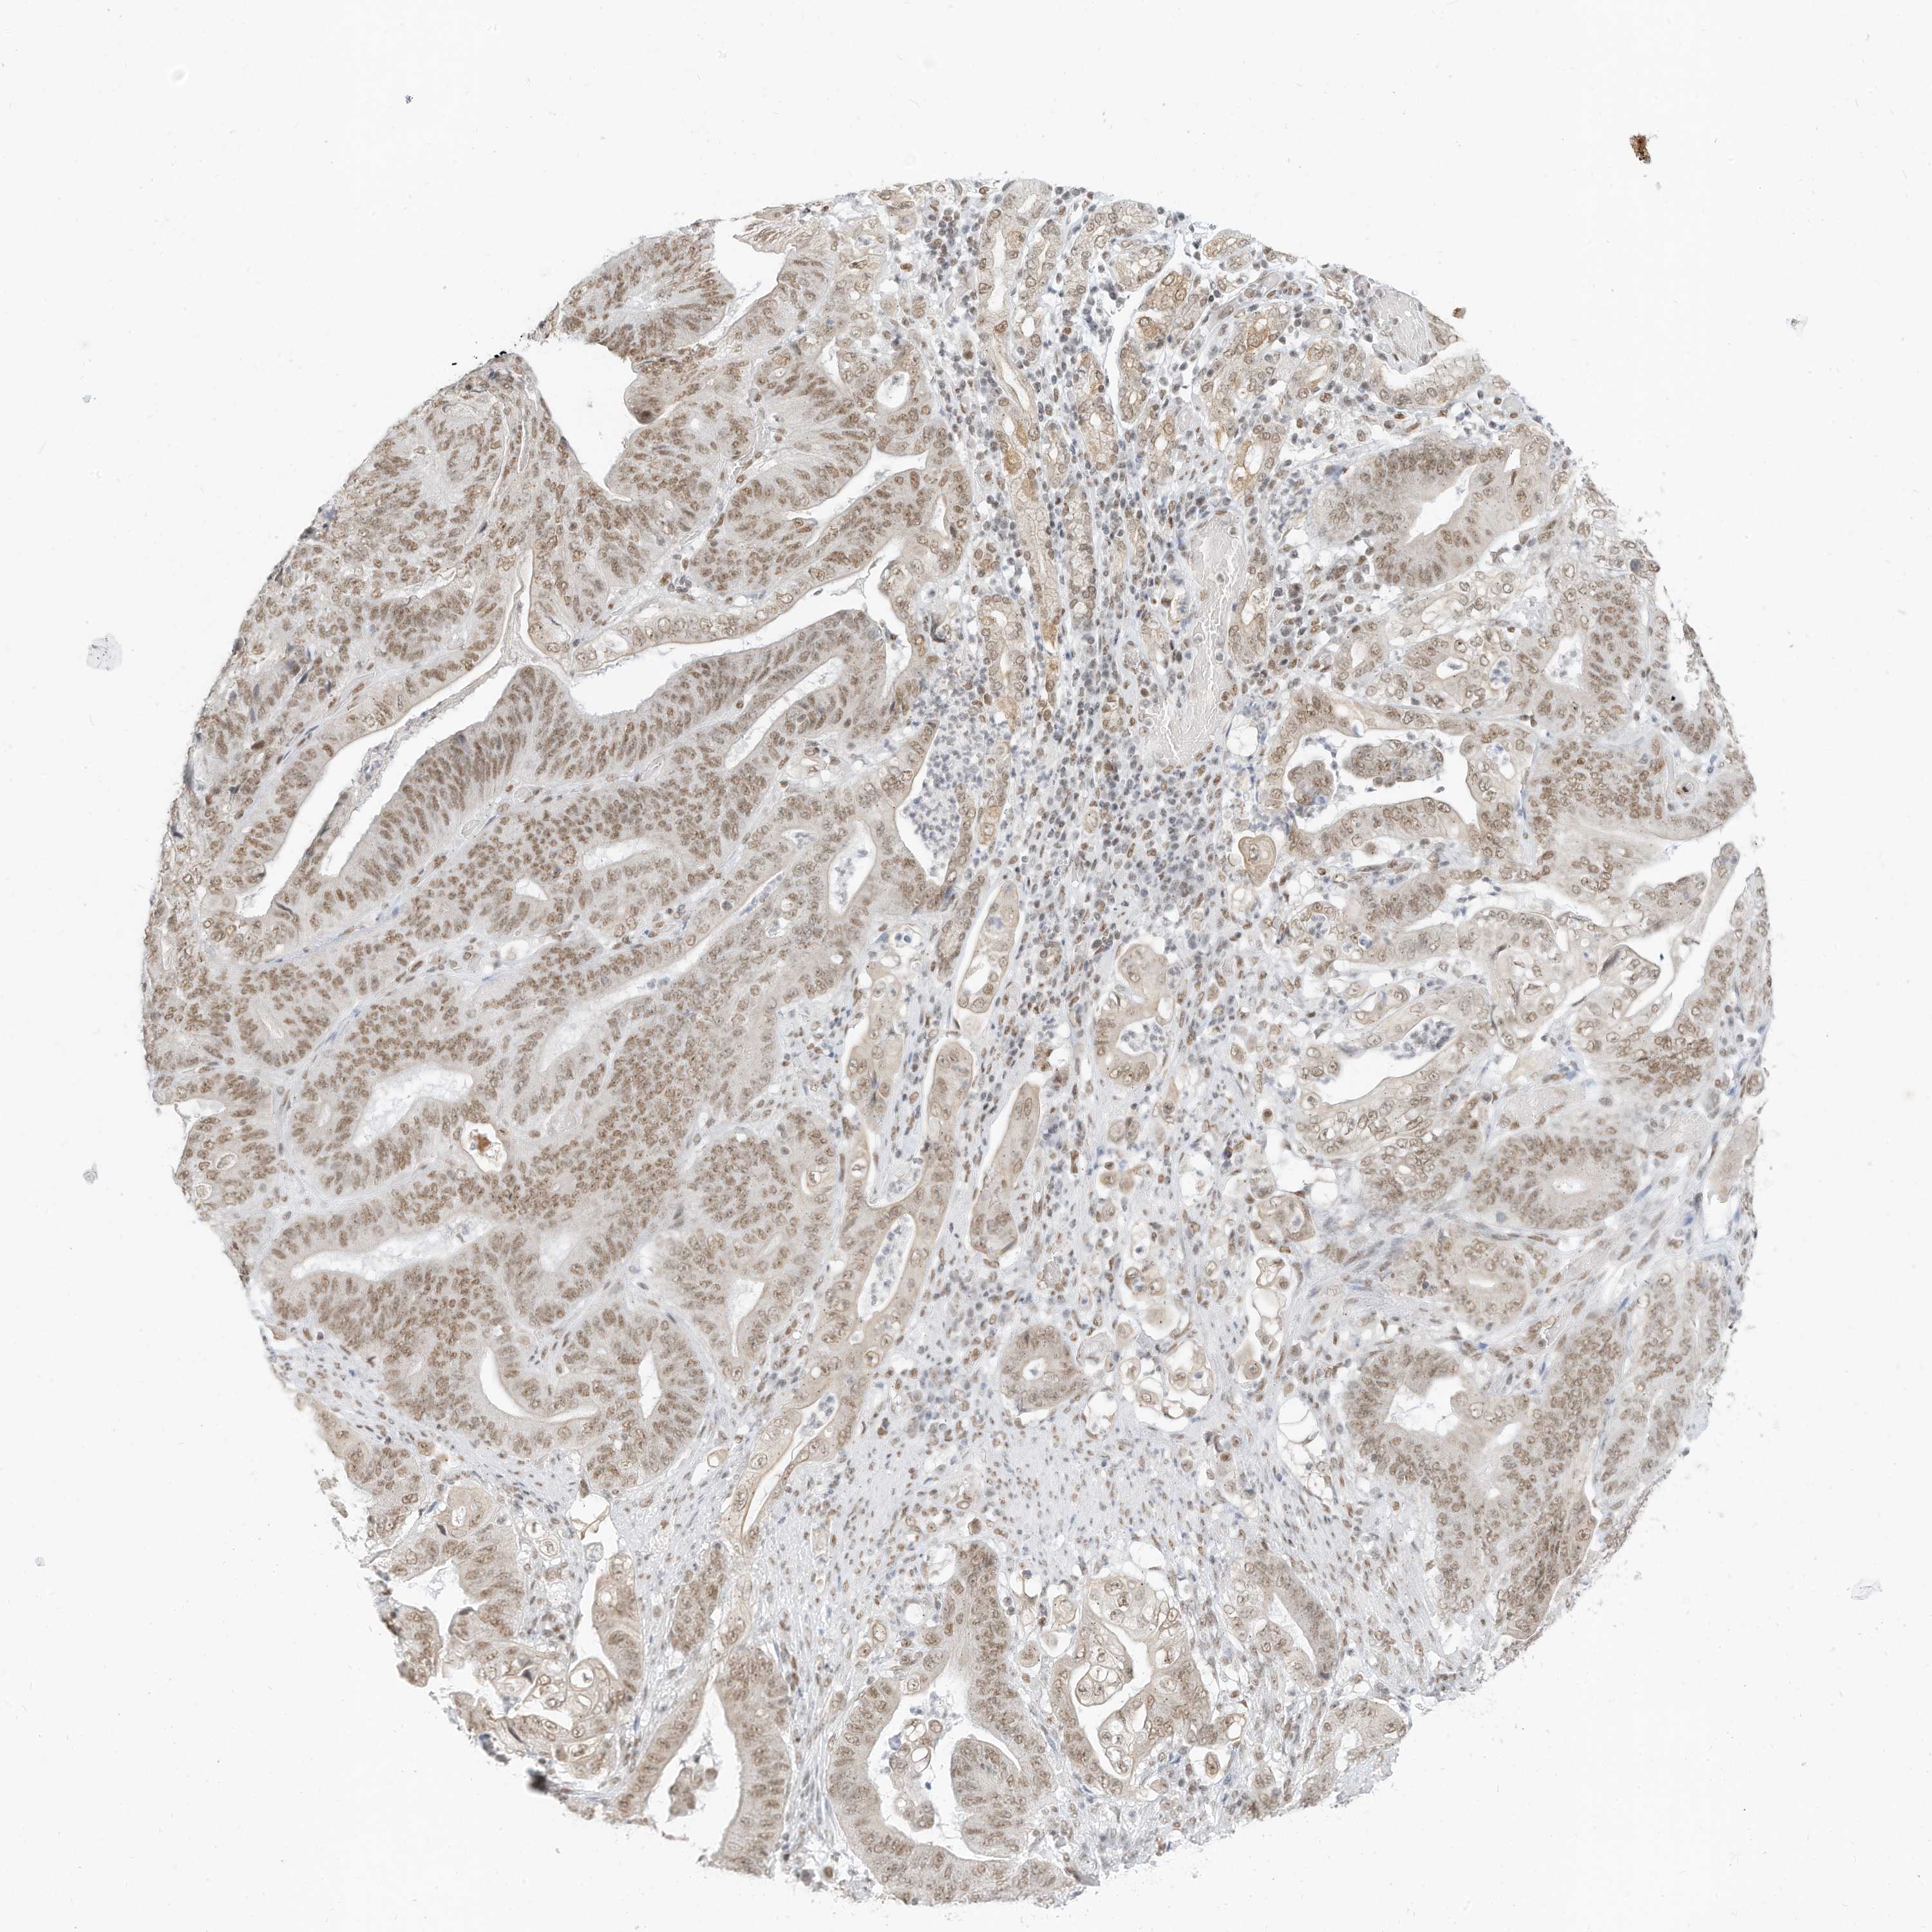

STOMACH CANCER - Protein expressioni

A mouse-over function shows sample information and annotation data. Click on an image to view it in a full screen mode. Samples can be filtered based on level of antibody staining by selecting one or several of the following categories: high, medium, low and not detected. The assay and annotation is described here.

Note that samples used for immunohistochemistry by the Human Protein Atlas do not correspond to samples in the TCGA dataset.

Antibody stainingi

Antibody staining in the annotated cell types in the current human tissue is reported as not detected, low, medium, or high, based on conventional immunohistochemistry profiling in selected tissues. This score is based on the combination of the staining intensity and fraction of stained cells.

Each image is clickable and will lead to virtual microscopy that enables deeper exploration of all samples and also displays staining intensity scores, fraction scores and subcellular localization as well as patient and tissue information for each sample.

Antibody HPA029981

Antibody CAB037276

Staining

High

Medium

Low

Not detected

Intensity

Strong

Moderate

Weak

Negative

Quantity

>75%

75%-25%

<25%

None

Location

Nuclear

Cytoplasmic/membranous

Cytoplasmic/membranous,nuclear

Adenocarcinoma, NOS